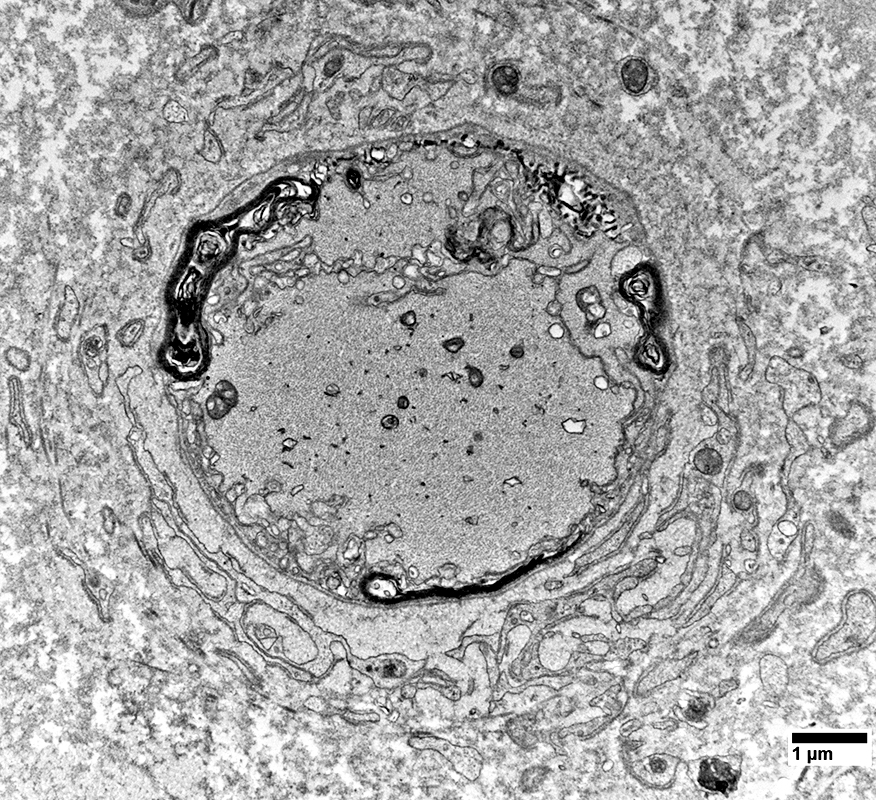

Myelinated Axons

A few have preserved structure

From: R Schmidt

Axons surronded by layers of Schwann cell processes

Schwann cells around Axons: Contain Myelin Degradation Products